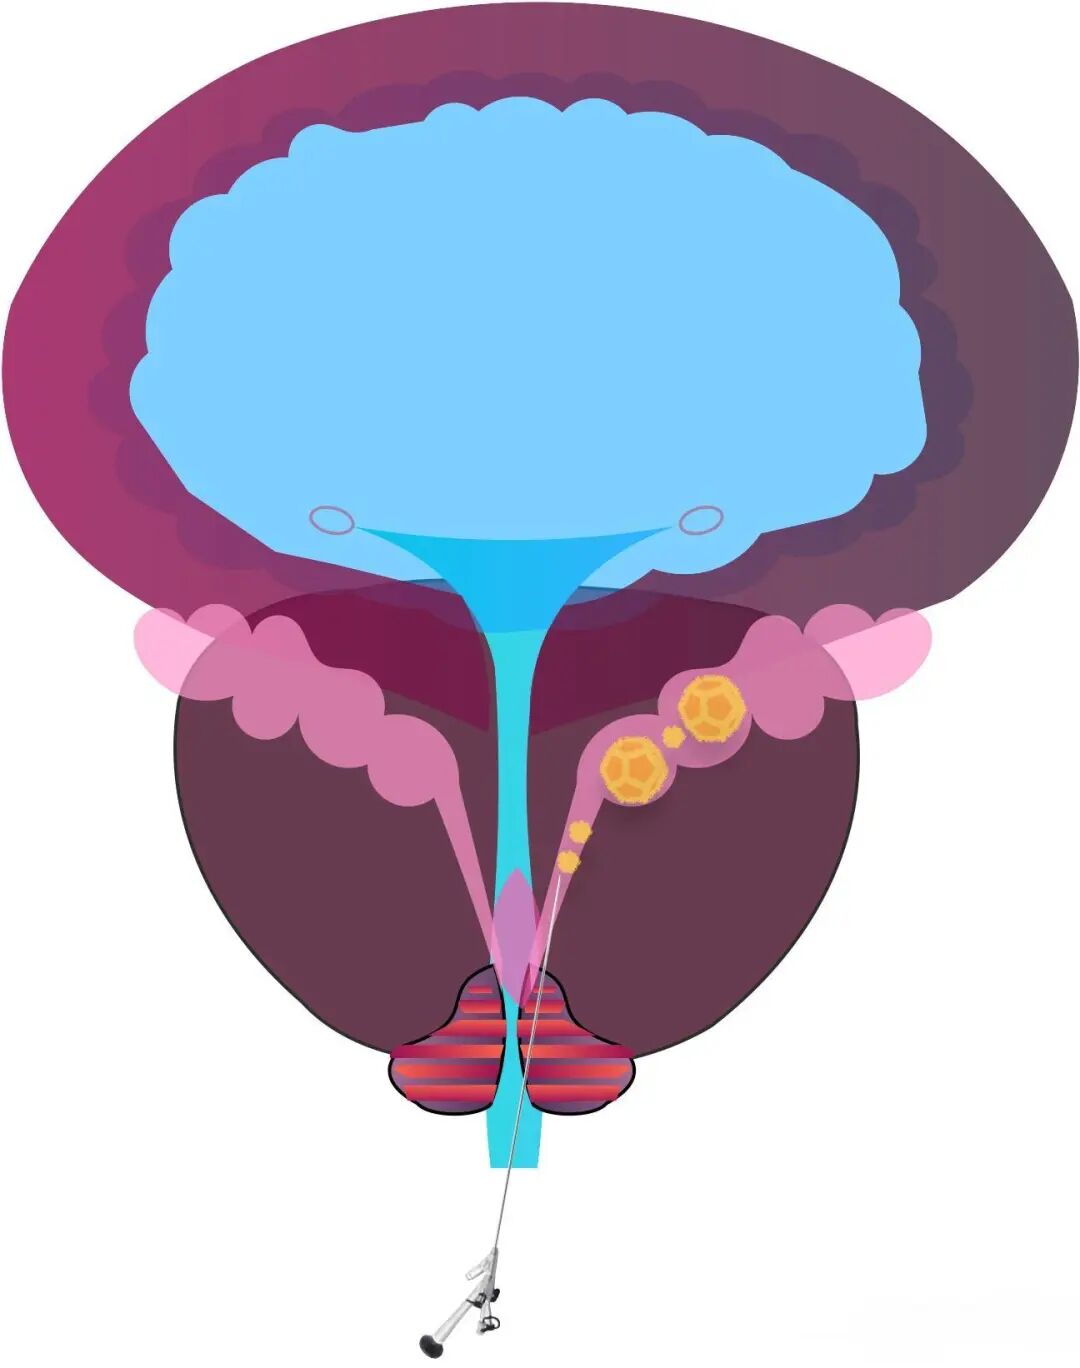

术中,李国成副主任医师通过细如笔芯的精囊镜,见患者射精管开口喷血,左侧精囊内结石,双侧精囊内黏膜有慢性炎症改变。最终,在精囊镜的导引下,精准定位结石,同步进行冲洗、取石和止血等操作,成功完成手术。

射精管出血

精囊内结石

炎症改变

什么是精囊镜技术

也叫精道内镜技术,是泌尿外科近10年发展起来的一项标志性新技术。运用比较细的内镜(通常为F4.5-F6.0)以及辅助器械,经正常精道或人工通道,对精囊进行观察及治疗,包括切开精道、冲洗、止血、活检、烧灼、引流、清除结石、解除梗阻等一系列手术操作。

✅ 精准治疗:高清影像“锁定”结石、炎症,同步完成冲洗、取石、止血,全程可视化操作,避免传统手术的并发症。